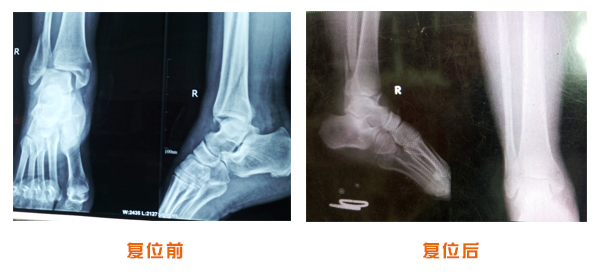

復(fù)位前后對比

踝關(guān)節(jié)脫位骨折治療前后對比